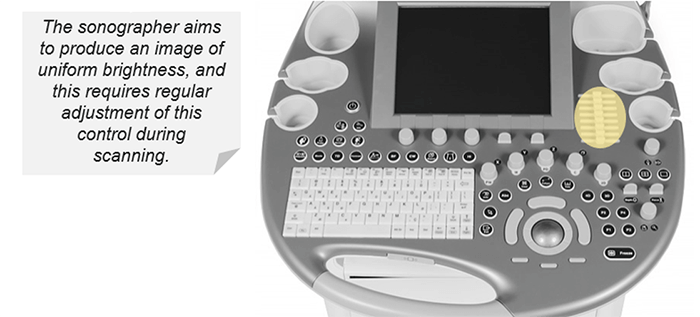

TGC

Since the ultrasonic waves are attenuated or absorbed, as they pass through the tissues, the reflected waves of the farthest areas are weaker than the waves reflected from the areas near the transducer. Without TGC, the image would have a gradual brightness ranging from light to dark (from the near field to the far-field).

TGC is an adjustment of the sensitivity at each depth, it allows the compensation of signal loss from deeper tissues. TGC is a series of multiple sliders so you can set the time-gain differently for each depth. This results in a uniform brightness in the entire field of view. For example, the TGC shall be set so that organs such as the liver will have uniform brightness at all depths.

To summarize, the T.G.C. compensates for the effects of attenuation by gradually increasing the amplitude of amplification applied to the signals as a function of the depth (time). The sonograph aims to produce a uniform brightness image from top to bottom, which requires regular adjustment during scanning.